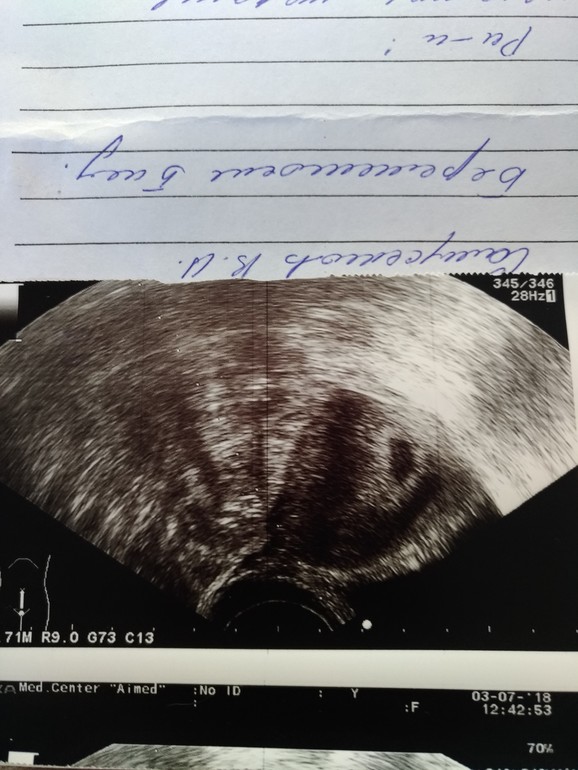

Первое УЗИ.

Я БЕРЕМЕННА !Вот я и сходила на первое узи.

Срок 5+2.

Нашли одно Плодное яйцо в матке (надеялась,что прижились двое).

Размер соответствует сроку.

Желточного мешка, эмбриона и сб, как и предполагалось еще не видно (но надежда была).